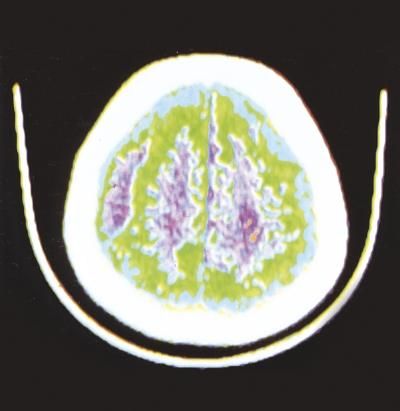

Per ematoma si intende una raccolta di sangue fuoriuscito dal sistema circolatorio e localizzata in un tessuto o in una cavità dell'organismo.

- traumi la cui forza vulnerante agisca su una struttura vascolare (ematomi da sezione diretta di un vaso) o sul tessuto o sull'organo che la contiene (lacerazione indiretta dei vasi come nell'ematoma muscolare, epatico o splenico, nell'ematoma cerebrale);

L'ematoma può interessare ogni struttura corporea e la sua gravità è legata, più che alla grandezza, alla sede in cui si sviluppa: